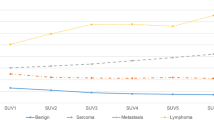

Lastly, the SUV thresholds used in the 12 studies that had evaluable SUV values were assessed to determine the optimal value that yielded enhanced sensitivity and specificity. Since two studies were outliers because of extremely low [18] and extremely high SUV values [22], they were excluded. Thus, the optimal SUV threshold value found with the remaining ten studies was 2.4 (Fig. 5).

The SUV cutoff value that best separated benign from malignant musculoskeletal soft tissue lesions was 2.4. Among the 12 studies analyzed, 10 reported a threshold between 2 and 4. Two studies were outliers. These discrepancies may be due to the type of lesion studied and/or the acquisition time. 18F-FDG uptake may increase with time in soft tissue malignancies and decrease with time in inflammatory lesions. In one study [22] the suggested optimal SUV cutoff value was 5.2; however, the authors included abscesses (which exhibit high uptake). In the other study [18] the suggested optimal cutoff was 0.8; however, the authors only evaluated lipomatous lesions (which have low uptake) and the images were acquired earlier (40 min after injection). The mean scan time among the 14 studies analyzed was 60 min. In one study [14] the images were acquired 120 min after 18F-FDG injection, and even though higher SUV values were expected to occur, still the optimal SUV cutoff for discriminating benign from malignant lesions in that study was in the range of 2.0 to 4.0 (SUV = 3.0).